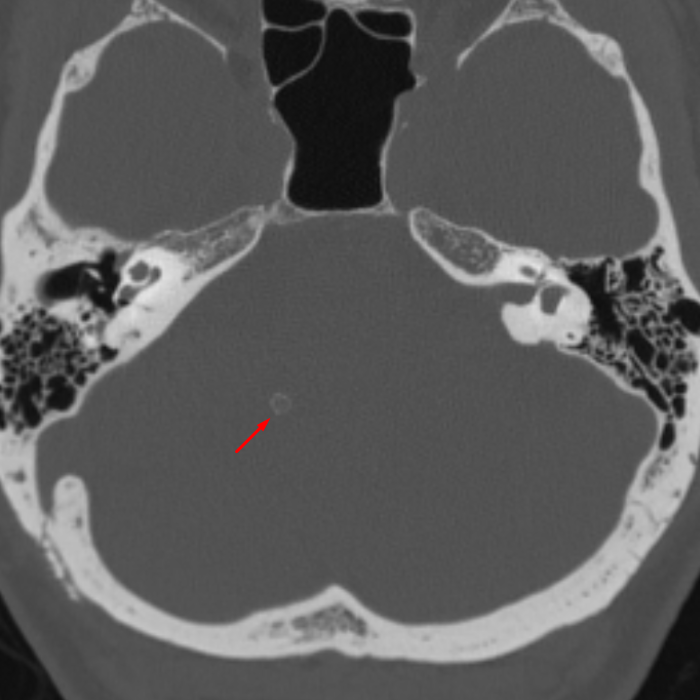

Age: 41

Sex: Male

Indication: Trauma